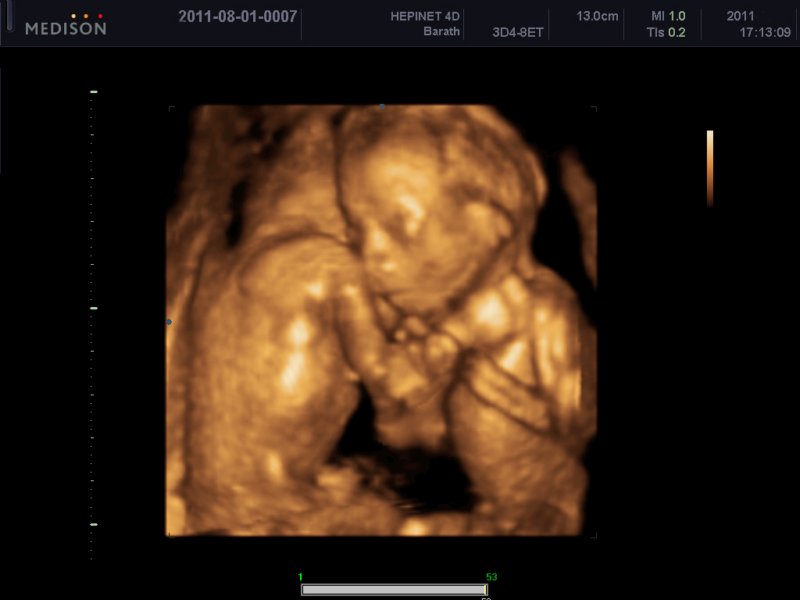

Ikerlányok